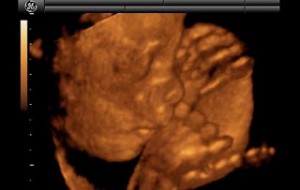

Bebeğin Boyutu: 43.7 cm, 1.9 kg

Hamileliğin (Gebeliğin) 35. Haftası Resim ve Video;